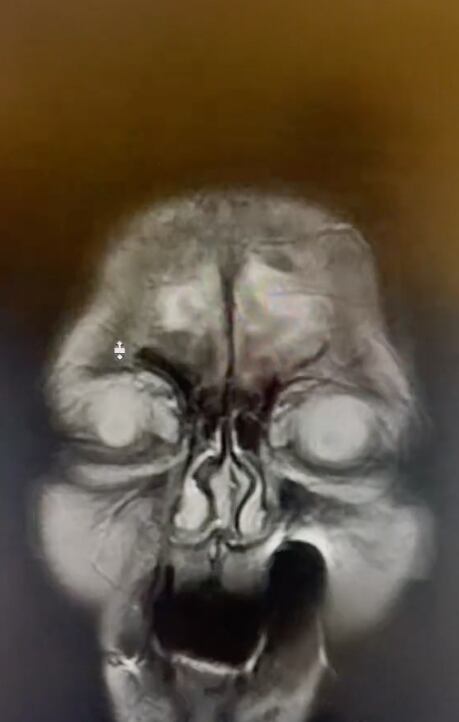

La resonancia magnética fue compartida por Luis A Mayora, @luismayorgaoficial en la plataforma, un tiktoker y radiólogo quien se dedica a compartir distintos casos médicos.

De acuerdo con el profesionista de la salud, la resonancia magnética se la hizo una mujer quien utilizó una aguja como palillo dental.

En su cuenta de TikTok, el radiólogo Luis A Mayora decidió compartir la resonancia magnética de una mujer quien utilizó una aguja en lugar de una palillo.

De acuerdo con el radiólogo, la punta de la aguja se le quedó en la encía, por lo que con su video pretendía advertir sobre el mal uso de accesorios para la higiene bucal.

Puesto que el desconocimiento por parte de los médicos sobre las causas de síntomas podría llevar a tratamientos erróneos.